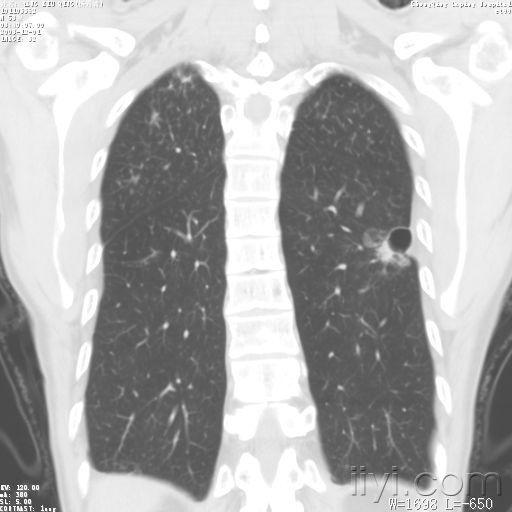

请各位老师指点,是肺气囊还是肺脓肿

肺气囊图片